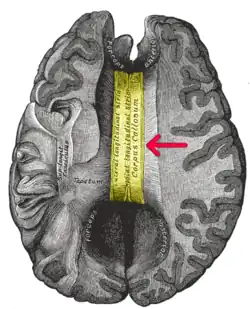

A corpus callosotomy (/kəˈlɔːs(ə)təmiː/) is a palliative surgical procedure for the treatment of medically refractory epilepsy.[1] The procedure was first performed in 1940 by William P. van Wagenen.[2] In this procedure, the corpus callosum is cut through, in an effort to limit the spread of epileptic activity between the two halves of the brain.[1]

Although the corpus callosum is the largest white matter tract connecting the hemispheres, some limited interhemispheric communication is still possible via the anterior and posterior commissures.[3] After the operation, however, the brain often struggles to send messages between hemispheres, which can lead to side effects such as speech irregularities, disconnection syndrome, and alien hand syndrome.

The corpus callosum is a fiber bundle of about 300 million fibers in the human brain that connects the two cerebral hemispheres. Its interhemispheric functions include the integration of perceptual, cognitive, learned, and volitional information.[11]